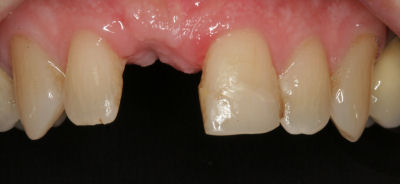

Implants have been around for many years and are a predictable method to replace missing teeth. They offer a way to have artificial teeth that look natural and feel secure. An oral implant is a titanium screw that is embedded into the jaw bone. Bone heals very tightly against the implant making the implant fixed to your jaw.

An implant replaces the root of the tooth to support a false tooth (implant crown). The dental surgeon, usually a Periodontist (gum specialist) or an Oral Surgeon, places the implant into a hole made in the jawbone during surgery. A post (abutment) is then be secured onto the top of the implant to secure the crown.

Implants are fixed to your jaw bone and do not move. This provides a stable platform to attach a single implant crown for the replacement of a single missing tooth. Implants are often favoured over fixed bridges supported by natural teeth, especially when the teeth adjacent to the missing tooth or teeth have not been filled.

By preparing teeth for a conventional tooth-supported bridge, a significant amount of tooth is cut away. In contrast, implant crowns can be more conservative, replacing a missing tooth while leaving adjacent teeth unaltered.